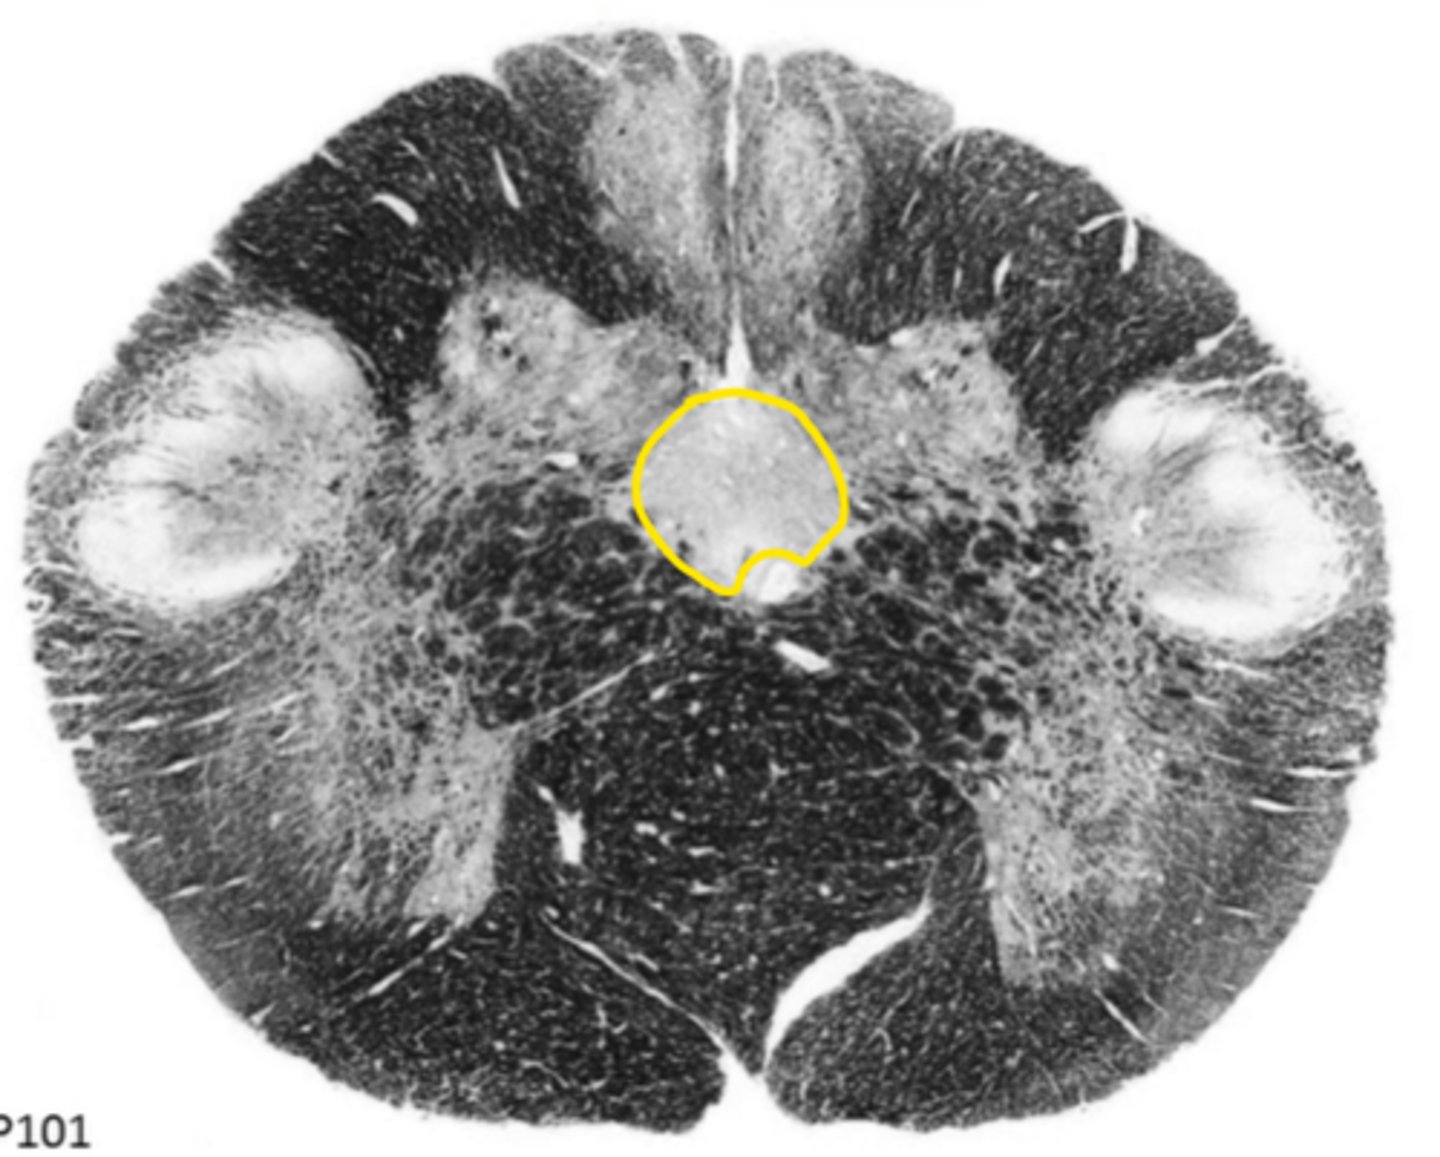

closed medulla

ID the brainstem level